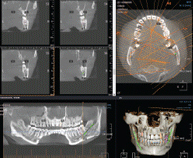

시작부터 다르다!

3차원 정밀진단 시스템

얼굴 골격을 빠짐없이 분석합니다

얼굴 골격의 모든 방향을 빠짐없이 촬영하고

치아와 치조골의 상태 및 잇몸뼈의 양과 길이 등의

전반적인 상태를 정확하게 측정하고 진단하여

한치의 오차 없는 시술로 진료의 안정성을 높힙니다.